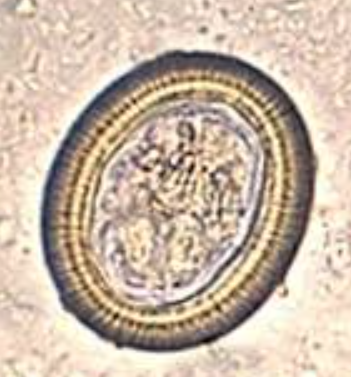

Toxocara canis/cati ova (low power)